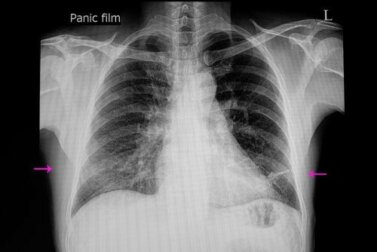

Per formulare la diagnosi di atelettasia sono in genere sufficienti la valutazione clinica e gli esami radiologici del caso. Tuttavia, è anche possibile impiegare determinate tecniche per confermare la diagnosi o stabilirne la gravità.

Tra questi troviamo la tomografia computerizzata, la broncoscopia, l’ecografia e l’ossimetria. La broncoscopia consente di osservare il tipo di ostruzione e persino di eliminarla.